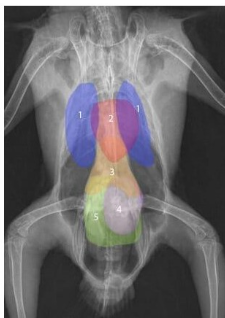

What species radiograph is this and what can we identify?

bird

blue = lungs

red = heart

rest = Gi tract - due to no diaphragm

What species and what can we identify here?